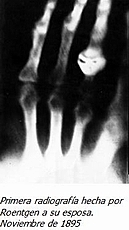

Sobre una mesa de madera, cerca de la ventana Roentgen, un 8 de Noviembre, realizando sus experimentos en el tubo de Hittorf-Crookes, descubrio de forma casual que se iluminaba el carton con el platinocianuro de bario. La primera radiografia que hizo en el laboratorio fue de la mano de Berta, su mujer.